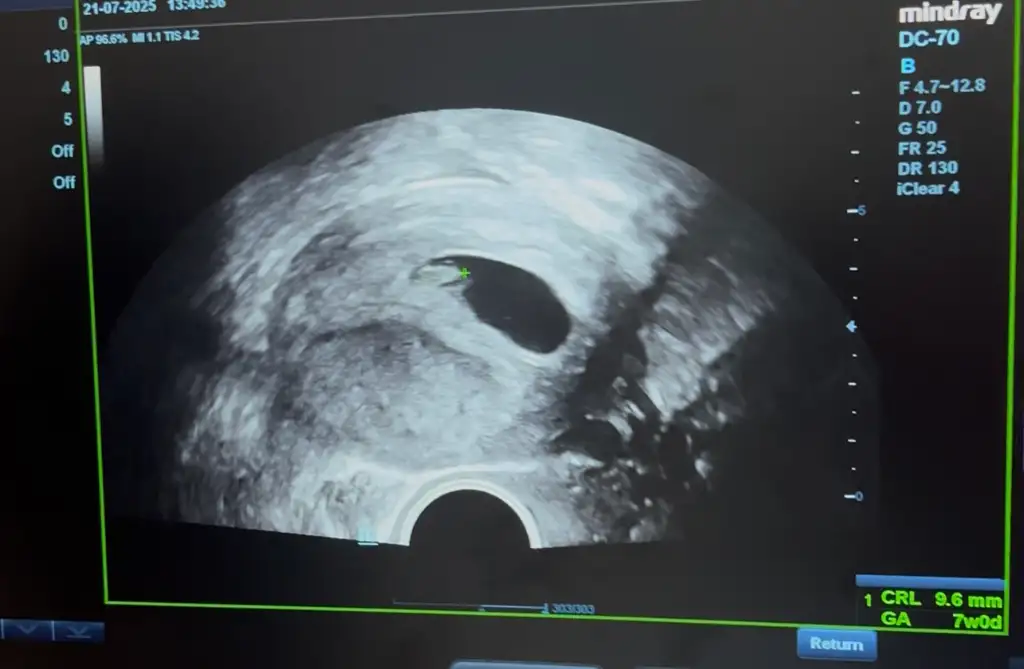

14 temmuzda 7+1 de gittiğimde kalp atışını duydum 9mm dedi haftasına göre biraz küçük dedi 4 Ağustos için randevu vardı duruma göre geri çekecek sanırım haftayı

21 temmuzda 8+1 de gittiğimde kalp atışını duydum 9mm dedi haftasına göre biraz küçük dedi 4 Ağustos için randevu vardı duruma göre geri çekecek sanırım haftayı

21 temmuzda biraz haftasına göre küçük dedi 15 gün yatak istirahati verdi tekrar geldiğinde büyümüş olursa sorun yok haftası ilerde gidiyordur dedi benimde kafam karıştı kaç gündür buraya bile yazmadım psikolojimi bozmayım diye ama yatmaklada vakit geçmiyor